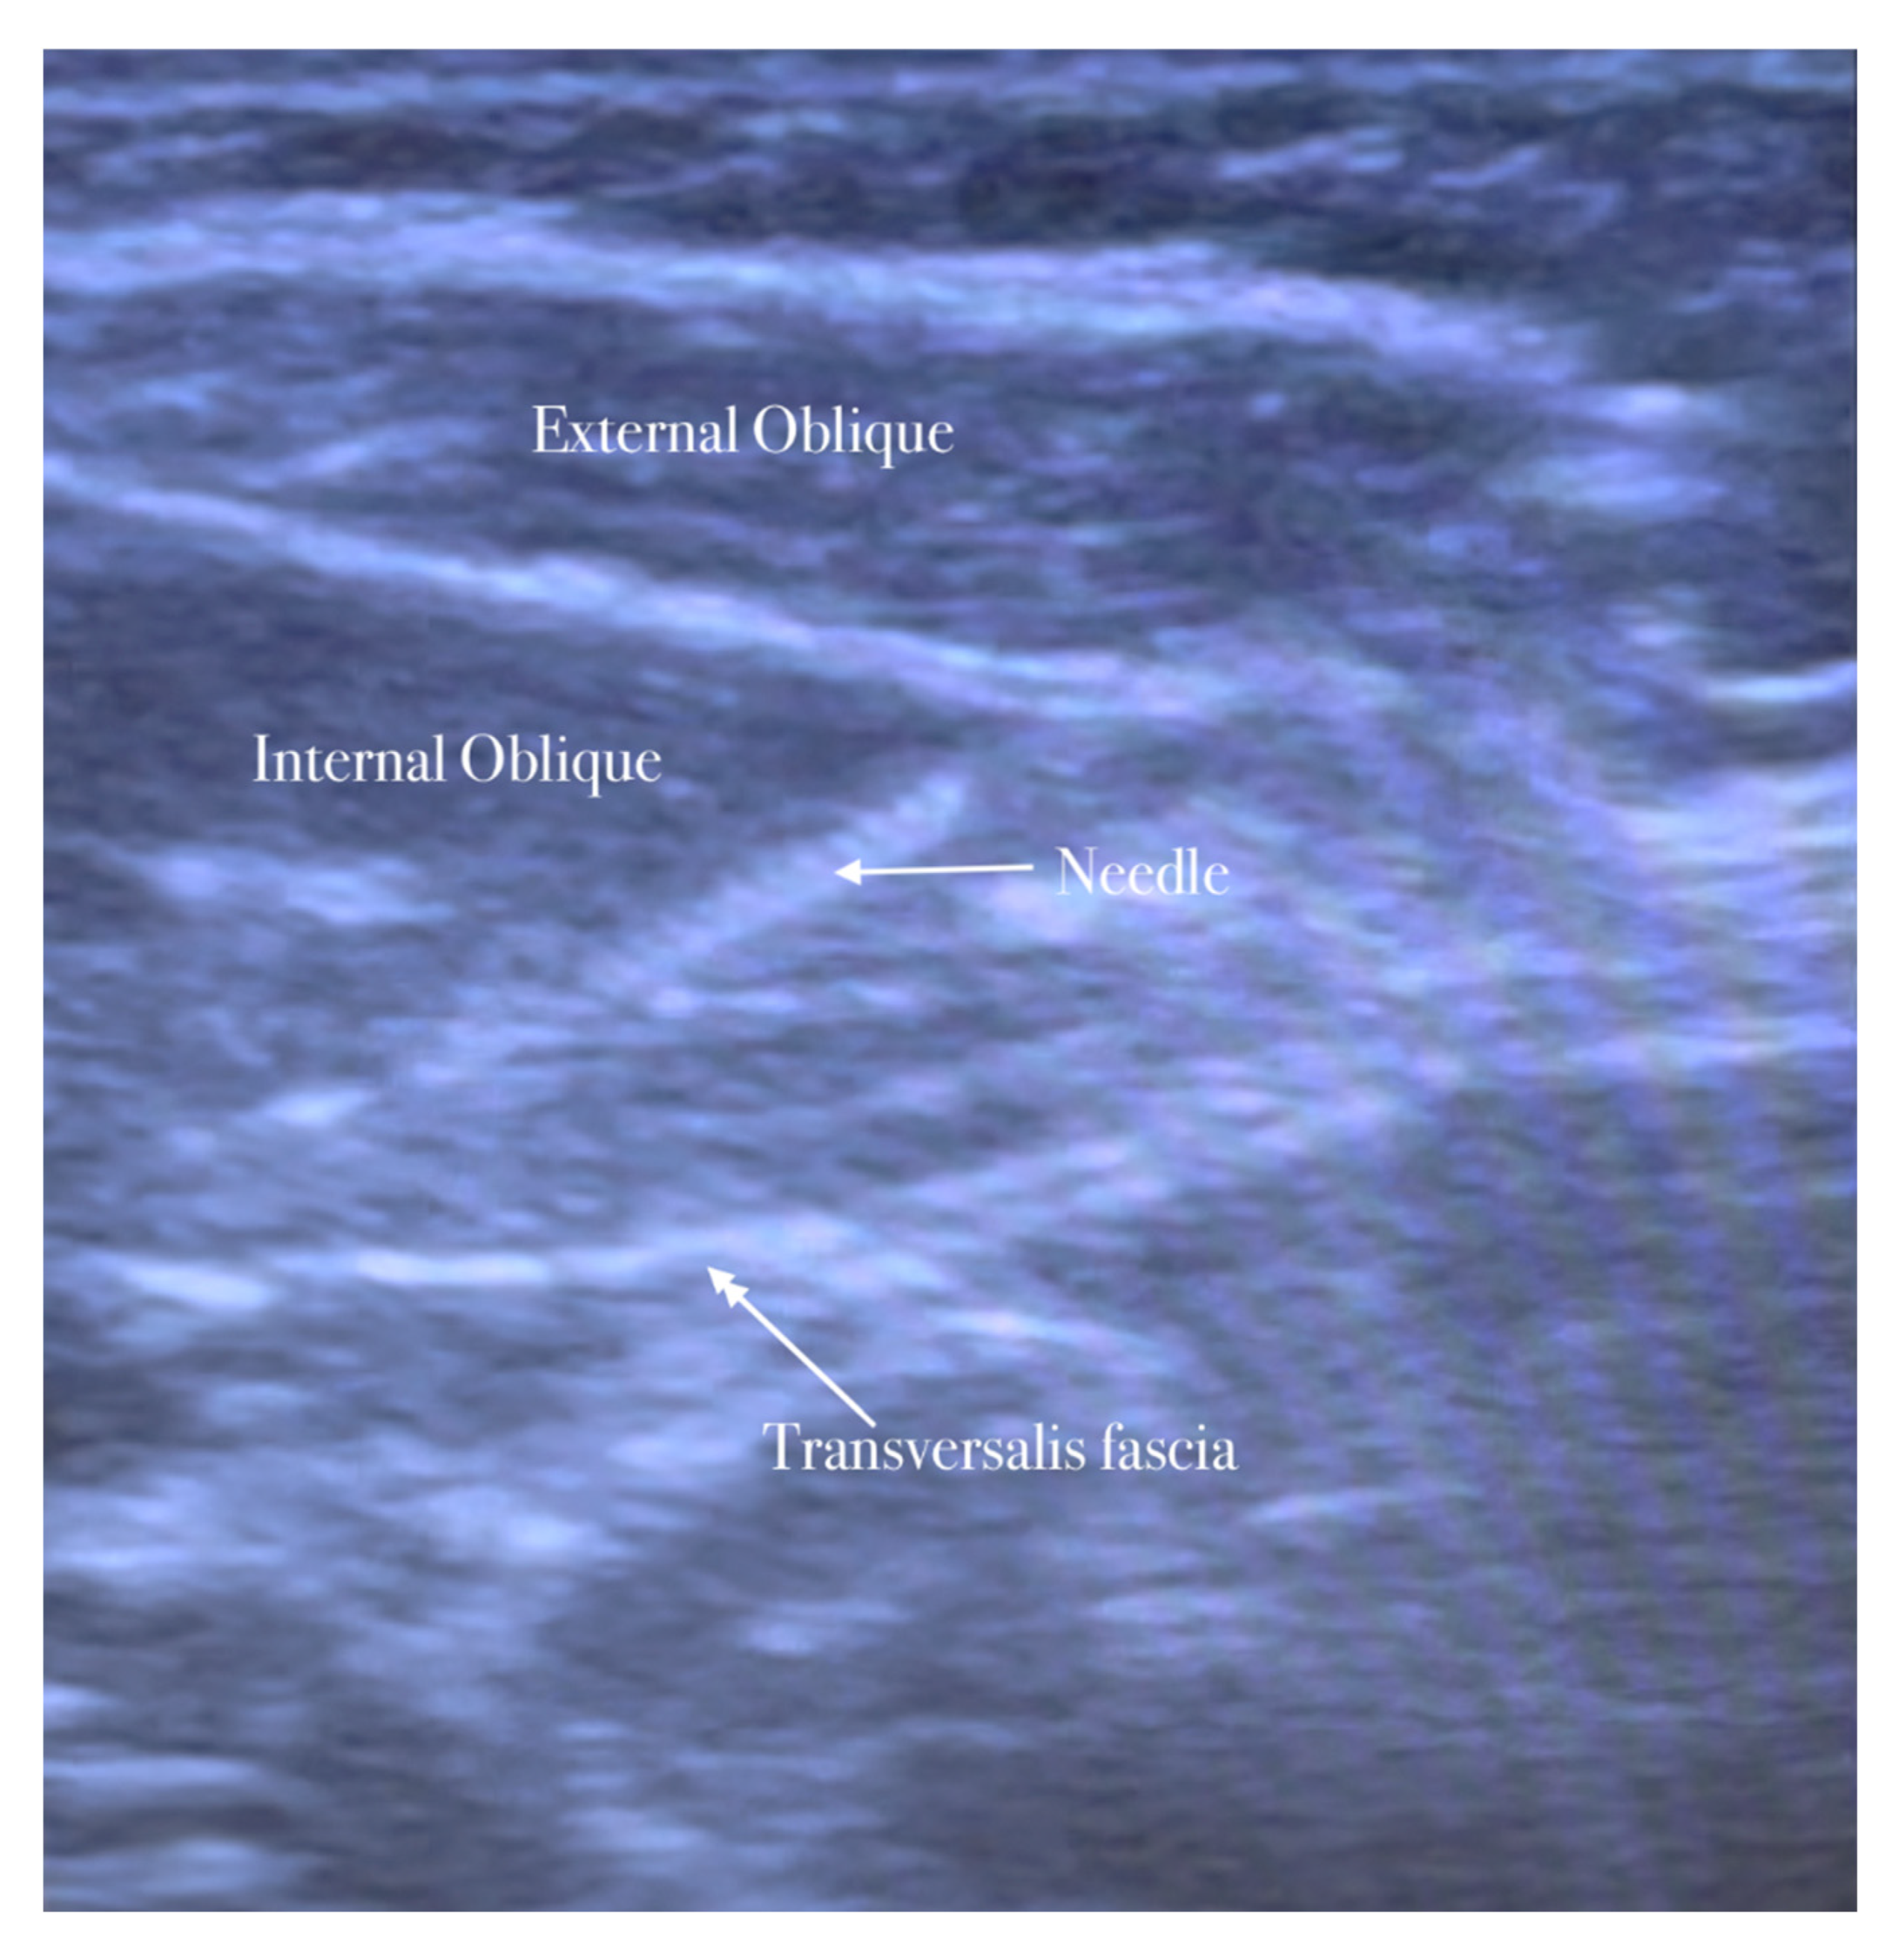

The needle is inserted in the plane in a medial-to-lateral direction; 10 mL of anesthetic (Mepivacaine 10 mg/mL–Ropivacaine 7.5 mg/mL) is injected in the transversus abdominis plane, as seen in Figure 1, Figure 2, Figure 3 and Figure 4.

The needle is inserted through the three abdominal muscles in the transversus abdominis plane.

5.2. Ilioinguinal–Iliohypogastric Nerves Block

The patient lies in a supine position. The ilioinguinal–iliohypogastric nerves block is performed unilaterally using ultrasound guidance and placed in the transversus abdominis plane. Ilio-hypogastric and ilioinguinal nerves are the terminal branches of the anterior rami of the L1 spinal nerve. They emerge from the upper part of the lateral border of the psoas major muscle; both nerves cross obliquely anterior to the quadratus lumborum and iliacus muscles and perforate the transverse abdominis muscle near the anterior part of the iliac crest. In the anterior abdominal trunk, the nerves travel between the transverse abdominis and the internal oblique muscles [15].

A high-frequency, linear, high-resolution probe is initially kept perpendicularly on the lateral abdominal wall at the midaxillary line between the anterior superior iliac spine and the navel. In this place, the three abdominal muscles are seen below the subcutaneous fat and the plane between the internal oblique, and the transversus abdominis muscle is identified. The peritoneum can be seen as the fascia layer underneath the transversus abdominis muscle. Between the layers of the transversus abdominis and the internal oblique muscle, the splitting of the fascia layer is usually observed. It is on this plane where the ilioinguinal and iliohypogastric nerves pass through. Sometimes, both nerves pierce the internal oblique and appear between the internal and external oblique muscles.